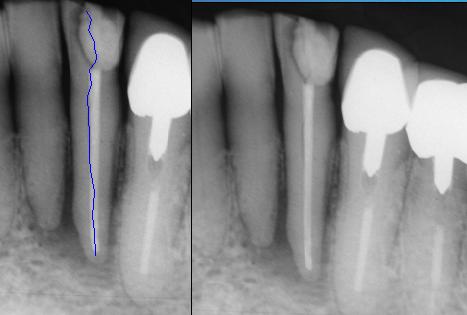

Men moet bedacht zijn op een endo/paro probleem als er een solitaire diepe bloedende pocket zit bij een vaak fors gevuld element. Zeker als er verder nauwelijks sprake is van parodontale problematiek. Patiënten geven soms aan dat ze bij “zuigen” een vieze smaak in de mond krijgen.

Uiteraard dient een X-foto te worden gemaakt. Soms is er een periapicale lucentie te zien.

Differentiaal diagnostisch moet er rekening worden gehouden met een fractuur. Gebruik van de behandelmicroscoop vergemakkelijkt de diagnose.